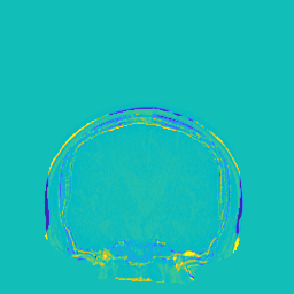

Model-based treatment planning for transcranial ultrasound therapy typically involves mapping the acoustic properties of the skull from an x-ray computed tomography (CT) image of the head. Here, three methods for generating pseudo-CT images from magnetic resonance (MR) images were compared as an alternative to CT. A convolutional neural network (U-Net) was trained on paired MR-CT images to generate pseudo-CT images from either T1-weighted or zero-echo time (ZTE) MR images (denoted tCT and zCT, respectively). A direct mapping from ZTE to pseudo-CT was also implemented (denoted cCT). When comparing the pseudo-CT and ground truth CT images for the test set, the mean absolute error was 133, 83, and 145 Hounsfield units (HU) across the whole head, and 398, 222, and 336 HU within the skull for the tCT, zCT, and cCT images, respectively. Ultrasound simulations were also performed using the generated pseudo-CT images and compared to simulations based on CT. An annular array transducer was used targeting the visual or motor cortex. The mean differences in the simulated focal pressure, focal position, and focal volume were 9.9%, 1.5 mm, and 15.1% for simulations based on the tCT images, 5.7%, 0.6 mm, and 5.7% for the zCT, and 6.7%, 0.9 mm, and 12.1% for the cCT. The improved results for images mapped from ZTE highlight the advantage of using imaging sequences which improve contrast of the skull bone. Overall, these results demonstrate that acoustic simulations based on MR images can give comparable accuracy to those based on CT.